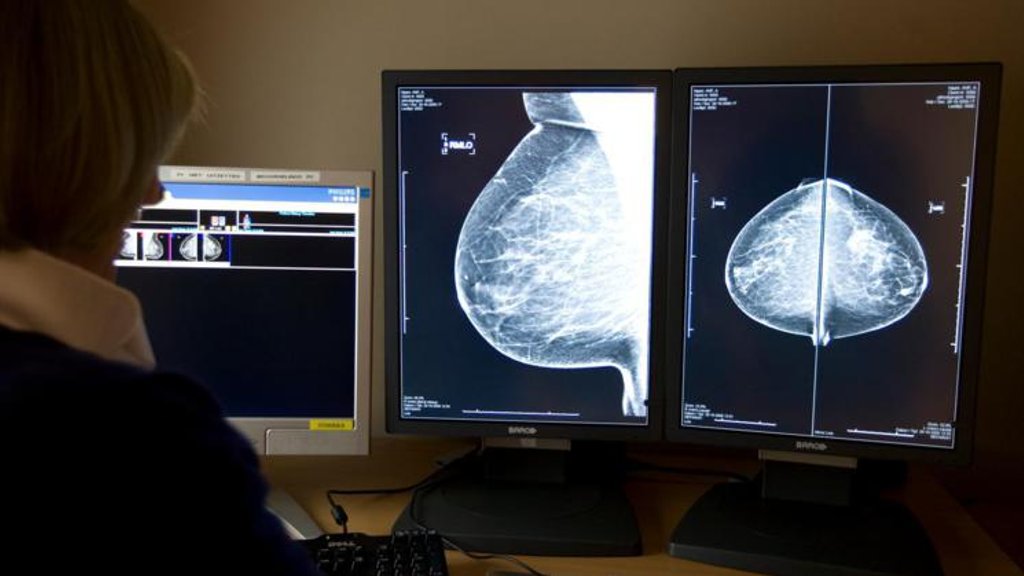

In Groot-Britannië is de 59-jarige chirurg Ian Paterson schuldig bevonden aan het verminken van twintig patiënten. Hij voerde ten onrechte verstrekkende borstoperaties uit, waarbij patiënten soms blijvende schade opliepen.

Het werkelijke aantal slachtoffers loopt waarschijnlijk in de honderden. Het is niet voor het eerst dat een chirurg zoiets doet. Een aantal jaar terug was gynaecoloog Rock Goerdin in het nieuws. Hij werd juist vrijgesproken van verminking, nadat het Openbaar Ministerie 3 jaar gevangenisstraf eiste tegen hem.